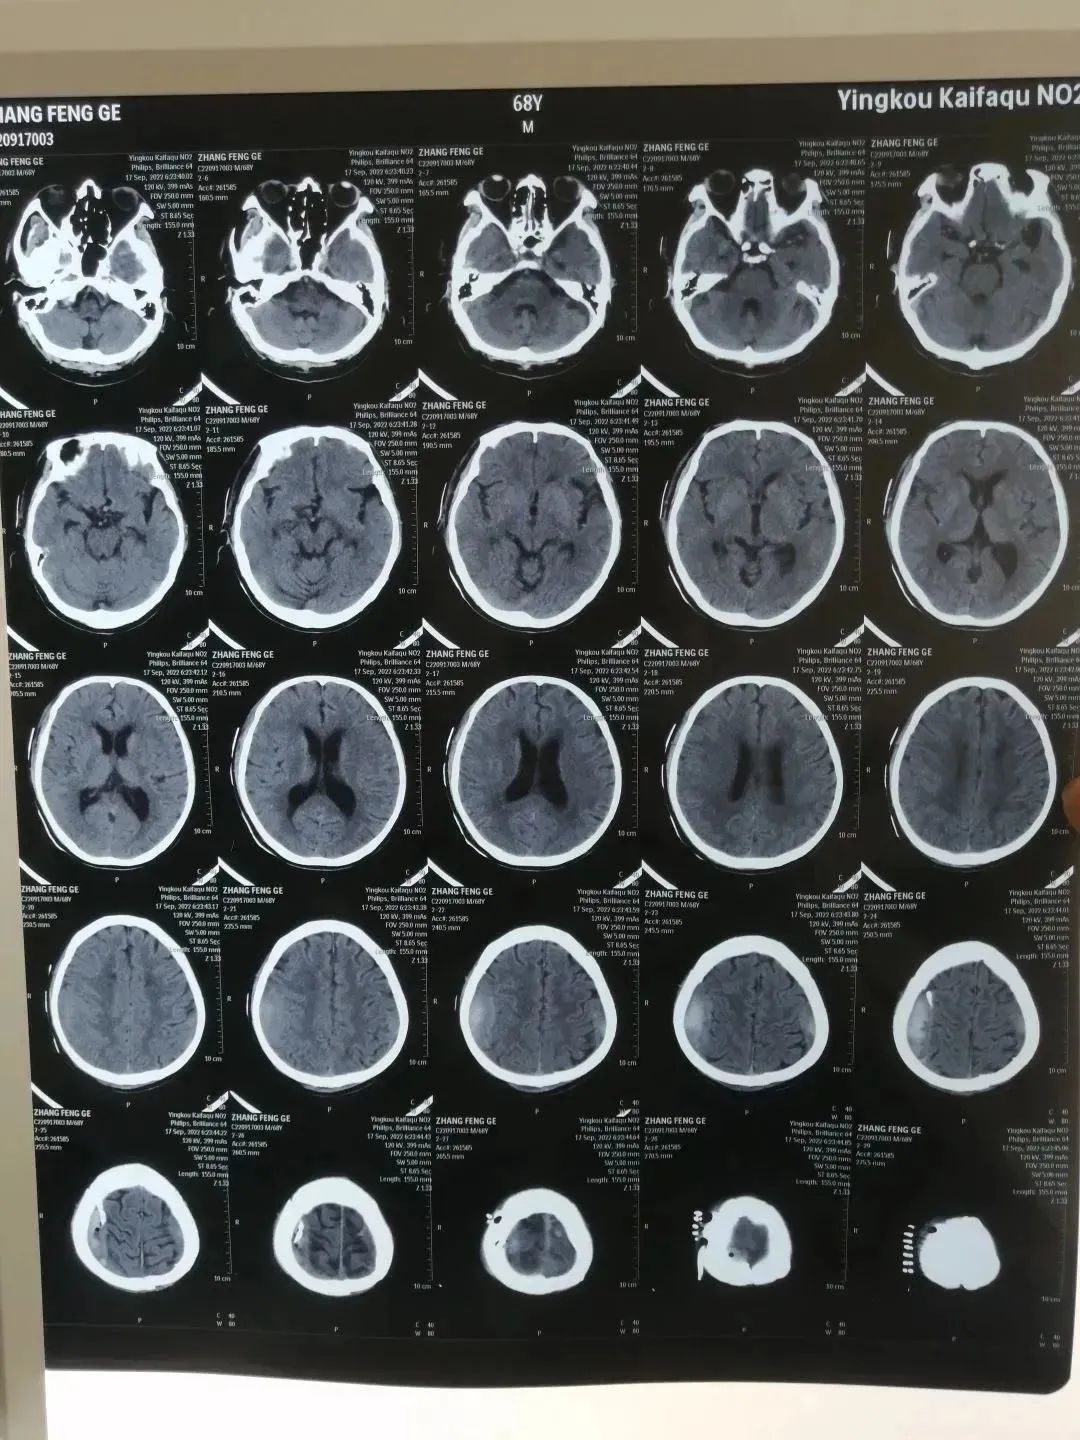

神经外科吕松林主任综合患者情况,拟定了周密的治疗计划,决定严密关注患者病情进展,通过注射脱水药物、白蛋白,保持呼吸道通畅等各种稳定颅压的措施,患者生命体征逐渐恢复了平稳。

(治疗后影像报告)

一周后,患者神志完全清醒。一个月后经过局部血肿引流术后,头痛症状明显缓解,现已顺利出院。